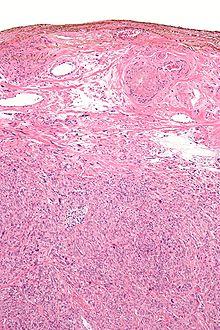

Micrograph showing a silver nitrate (brown) marked surgical margin.

Silver salts have antiseptic properties. In 1881 Credé introduced the use of dilute solutions of AgNO3 in newborn babies' eyes at birth to prevent contraction of gonorrhea from the mother, which could cause blindness. (Modern antibiotics are now used instead.)[16][17][18]